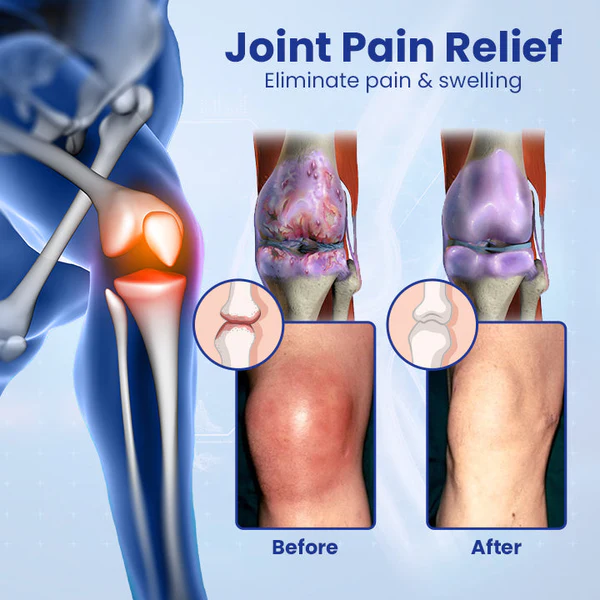

Joint pain is caused by a variety of causes, including inflammatory joint disease, fractures and injuries, aging, infections, metabolic problems and lifestyle factors. These conditions lead to arthritis, joint pain and limited range of motion, which can negatively impact the quality of life of those affected that interfere with their ability to lead active and fulfilling lives.

Ceoerty™ JointRenew Bone Repair Gel Roller has been carefully designed to relieve joint discomfort, stiffness and inflammation. Its unique roll-on formula quickly penetrates the skin and delivers a blend of natural anti-inflammatory ingredients exactly where they are needed. This fast-acting blend provides rapid relief from joint discomfort and stiffness, allowing you to carry out your daily activities comfortably. Designed with precision, it aims to provide targeted relief for joint and bone pain by delivering a combination of organic ingredients directly to the area in need of relief.

✓ Targeted relief for joint problems

✓ Relieves stiffness and inflammation